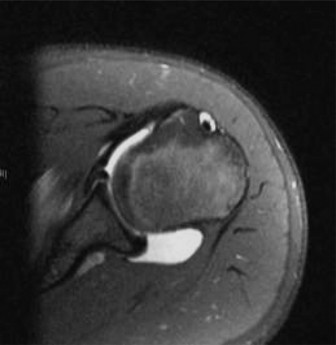

The correct answer is (C). 3D-CT is a powerful test to evaluate osseous anatomy and injury. However, it is not the best test to evaluate injuries that primarily involve soft tissue, such as labral or cartilage lesions. Additionally, CT imaging carries with it an inherent risk of exposure to radiation, which ideally is avoided in young patients. While an MRI of the shoulder with and without IV contrast may be useful in this setting, it is unlikely to be as useful for evaluating labral pathology as an MRI arthrogram. An MRI arthrogram of the shoulder, in which radiopaque dye is injected into the shoulder prior to image acquisition, is the “gold standard” test for evaluating labral pathology. The MRI arthrogram for patients with labral tears will exhibit a characteristic appearance in which the dye “turns the corner,” tracking underneath the labrum and around the glenoid (see Figure 10–38). dGEMRIC MRI is most helpful for assessing cartilage injury. Three-phase bone scans may be used to identify areas of high metabolic activity (such as tumor, injury, or infection) but would not be useful in this setting.

Figure 10–38 T2 axial image of an MRI arthrogram of the shoulder, exhibiting an anterior labral tear.